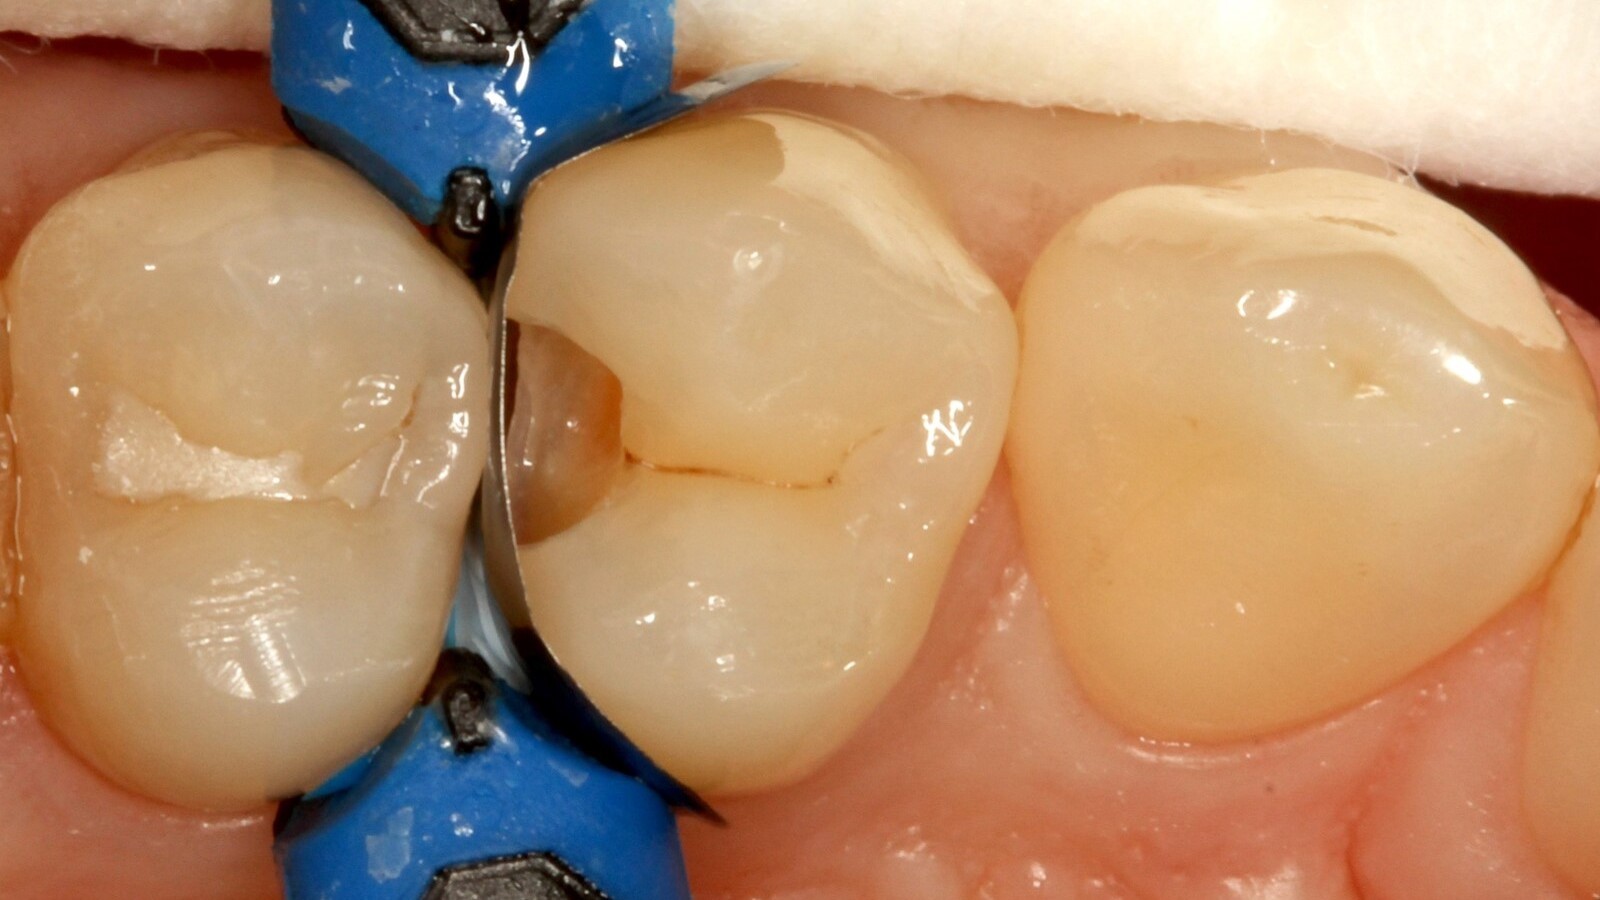

Le professeur Ernst a d'abord identifié les caries non visibles et a ouvert la lésion carieuse pour montrer le problème au patient (Fig. 1-2). Il a ensuite excavé la carie, préparé la cavité et placé une matrice sectionnelle (Fig. 3) avant de sceller la cavité avec de l'adhésif (Fig. 4). En une seule étape, il a rempli la cavité avec Venus Bulk Flow ONE (Fig. 5). Une fois la restauration terminée, le Pr Ernst l'a polie (Fig. 6) et a pris une radiographie de contrôle, qui montre également l'excellente radiopacité de Venus Bulk Flow ONE (Fig. 7).